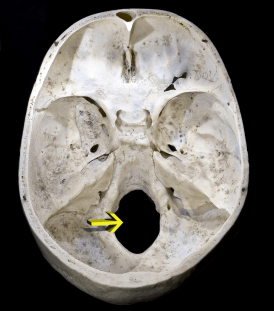

If there wasn’t a way for the brain to communicate with all of your organs, tissues and muscles, you’d be a vegetable. So one of the most important parts of the body is a “hole” in your head called the Foramen Magnum. This is where a critical area of your brain known as the brainstem exits the skull and becomes the spinal cord.

Resting directly beneath the Foramen Magnum is the first spinal segment, better known as atlas or C1. This 2-oz ring shaped structure possesses a considerable degree of mobility relative to the other 23 bones of your spine. The persistent motion required by this region of the spine makes it the most prone to misalignment.

Though often subtle, this spinal segment can apply just enough pressure or irritation to compromise the “hole” in your skull, causing an imbalance between the head and neck. Muscles, ligaments and joints will compensate asymmetrically, effecting blood flow and in many cases, altering nerve transmission.

[…] image above shows the base of the skull where the brainstem passes through the foramen magnum. The root/vine-like tubes seen here are blood vessels. This picture demonstrates important blood […]